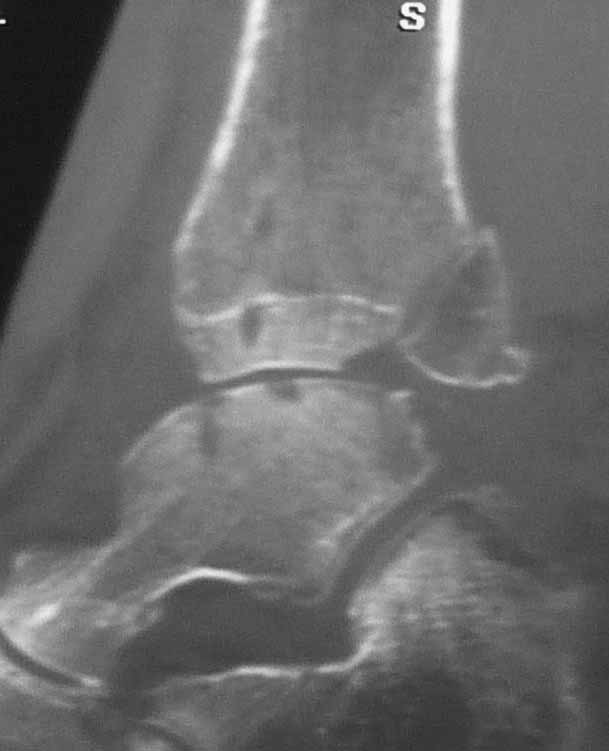

Уважаемые коллеги. Не так давно на форуме коротко обсуждались возможные последствия

трансартикулярной фиксации голеностопного сустава при переломовывихах лодыжек.

На днях довелось увидеть КТ после удаления спиц. Картинки наглядные и, практически, не

нуждаются в комментариях. Одна из спиц, кстати, проходила через фрагмент заднего края.